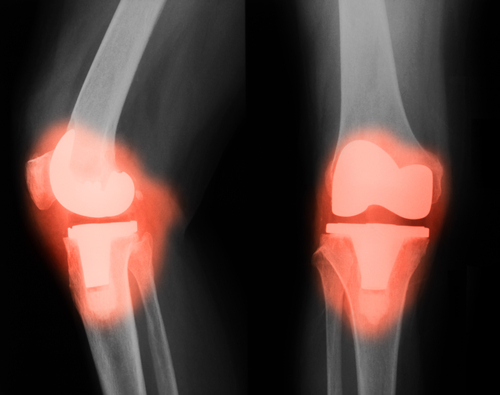

Η Ολική Αρθροπλαστική Γόνατος με την τεχνική ελάχιστης επεμβατικότητας που προστατεύει τον τετρακέφαλο μυ (Quadriceps-Sparing ΜΙS) είναι μια νέα χειρουργική μέθοδος που επιτρέπει στον εξειδικευμένο Ορθοπαιδικό χειρουργό να τοποθετήσει τα σύγχρονα, εξαιρετικά επιτυχημένα και ανθεκτικά στο χρόνο εμφυτεύματα της αρθροπλαστικής μέσω πολύ μικρότερης τομής από ότι στο παρελθόν και μιας χειρουργικής προσπέλασης που αποφεύγει τον τραυματισμό του πιο σημαντικού μυός του γόνατος, του τετρακέφαλου μυός. Αυτή η νέα χειρουργική τεχνική όχι μόνο χρησιμοποιεί μια μικρή τομή στο δέρμα που τυπικά είναι γύρω στα 8 εκ., αλλά σέβεται τα μαλακούς ιστούς της άρθρωσης και κυρίως τον εκτατικό μηχανισμό του γόνατος, που είναι το πιο σημαντικό στοιχείο για την άμεση και ανώδυνη κινητοποίηση του ασθενούς μετά το χειρουργείο. Ο ατραυματικός χαρακτήρας μιας τέτοιας αρθροπλαστικής προσφέρει στον ασθενή ταχύτερη ανάρρωση, σαφώς λιγότερο μετεγχειρητικό πόνο, πλήρως ανεξάρτητη βάδιση μέσα στις 2 πρώτες εβδομάδες μετά το χειρουργείο και άμεση επιστροφή στην καθημερινότητά του.

- Άμεση επιστροφή της κινητικότητας και της απρόσκοπτης λειτουργίας της νέας άρθρωσης: Οι ασθενείς που υποβάλλονται σε αρθροπλαστική γόνατος με τεχνική ελάχιστης επεμβατικότητας αποδεικνύεται ότι αναλαμβάνουν τον έλεγχο της μυϊκής ισχύος, την κινητικότητα και τη λειτουργικότητα του γόνατος πολύ πιο γρήγορα. Αυτό συμβαίνει λόγω του ότι το χειρουργικό τραύμα δεν περιλαμβάνει την κακοποίηση του μηχανισμού της έκτασης του γόνατος που αποτελούσε αναγκαίο κακό στο παρελθόν: ο τένοντας του τετρακεφάλου μυός προστατεύεται και η επιγονατίδα δεν αναστρέφεται αλλά απλά παρεκτοπίζεται στο πλάι της χειρουργικής τομής.

- Μικρότερη χειρουργική τομή. Αν και το καλύτερο κοσμητικό αποτέλεσμα είναι από τα λιγότερο σημαντικά οφέλη αυτής της τεχνικής, η τομή στο δέρμα και το επακόλουθο χειρουργικό τραύμα έχει περίπου το μισό μέγεθος σε σχέση με τις παραδοσιακές αρθροπλαστικές γόνατος.